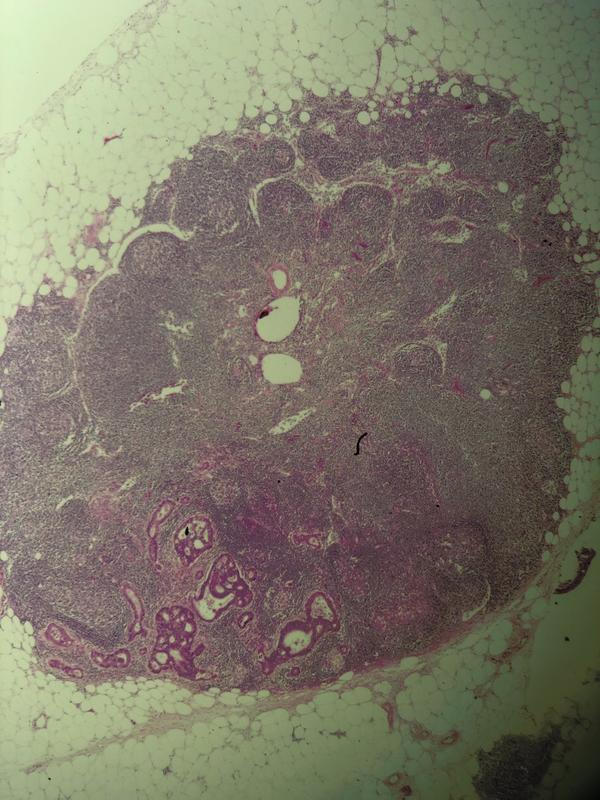

Metastatic Adenocarcinoma in a lymph node.

Metastatic Adenocarcinoma (bottom left) in a lymph node.

Leaving my slowly developing comfort zone of dentistry, I entered a laboratory where potions and chemicals were stacked high on bench worktops and white lab coat scientists filled the room. In the microscopic reporting room, tissues from every aspect of a patient’s body were reviewed and examined to determine a diagnosis. Our first exercise was to evaluate an axillary lymph node biopsy that had been taken from a lady. A myriad of colours exploded from the circular microscope field as we slowly turned the wheel to move around and tried to work out what we were looking at (albeit with one eye closed).

The consultant explained all the normal features and highlighted the metastatic carcinoma present which was responsible for the swelling. The markers found on a cell surface or specific proteins in a nucleus can be detected using special stains (known as immunohistochemistry) and can help determine where this carcinoma had originated from but to my surprise, some organ cancers have a particular look about them which the experienced eye can detect. ‘This is breast cancer, I can tell by the way the cells look, I just need to confirm this with my stains’ the consultant informed. Sadly for this patient, a lump in her armpit will be the start of her cancer pathway.